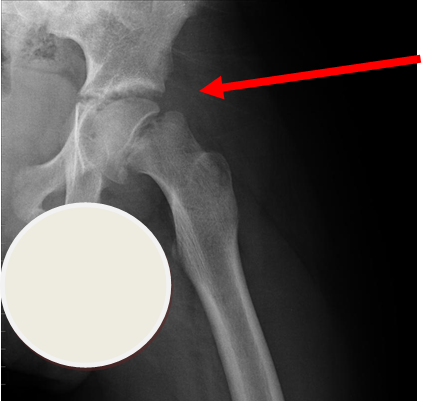

Lateral view of same patient as above

Case courtesy of Dr Gagandeep Singh, Radiopaedia.org. From the case rID: 7228

Usually occurs in late childhood / adolescence and is more common in boys than girls (2:1). It also presents more commonly in children whose weight is above the 90th centile. Bilateral in 25% of cases. Onset can be acute or subacute (ie children may present with >1day h/o pain or limp). Children may walk with an antalgic gait out-toeing, with shortening of the affected limb. If the slip is acute, the child may be unable to walk. Diagnosis is made radiologically and frog-lateral views are required as it may be missed on AP views. Urgent orthopaedic opinion is required. Unstable slips can lead to avascular necrosis of the femoral head.

Investigation

- X-ray - AP pelvis with frog lateral view (must be discussed with ortho 1st on call / ED consultant if child <8 years old)